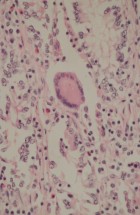

The Department’s main activities encompass research and specialized tasks. It focuses on clinical, pathoanatomical, pathohistological, immunohistochemical, and molecular diagnostics of diseases in both domestic and wild animals, including reproductive pathology. Operations within the department are structured around fieldwork and laboratory analyses.

- Performing pathohistological, cytological, immunohistochemical, and molecular diagnostics.

- Diagnosing transmissible spongiform encephalopathies in cattle, sheep, and goats.